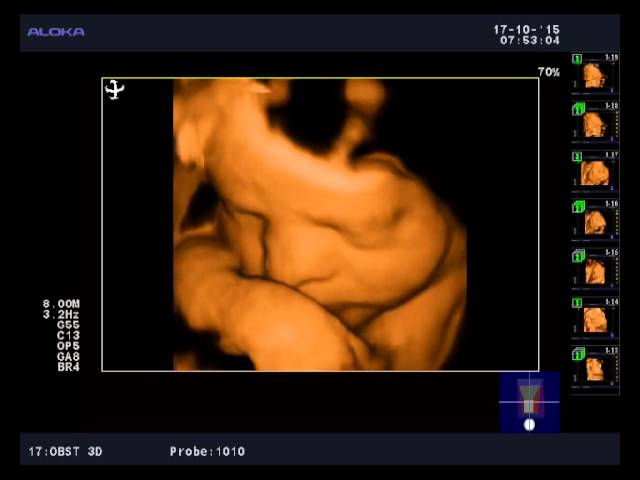

Если снимки выполняют посредством 3D УЗИ, то на фотографии можно рассмотреть радужную оболочку глаза.

В этот период беременности можно наблюдать в процессе УЗИ эмоциональную активность плода, а также рассмотреть первые движения ребенка, его способность сосать палец. После ультразвуковой диагностики мама получит симпатичное фото своего крохи.

Что интересно — на сроке 31 неделя беременности при УЗИ на фото и видео уже можно достаточно подробно рассмотреть черты лица ребенка.

Конечно, цвет глаз еще не рассмотреть (хотя радужная оболочка в этот период уже начинает приобретать свойства взрослого глаза и реагирует на яркий свет), но сейчас все более популярной становится технология 3D и 4D УЗИ, которая дает наибольшие возможности в визуализации плода.

Это УЗИ позволяет оценить степень развития головного мозга и других внутренних органов. Если УЗИ на 31 неделе проводится в 3Д или 4Д формате можно четко увидеть все очертания лица ребенка.